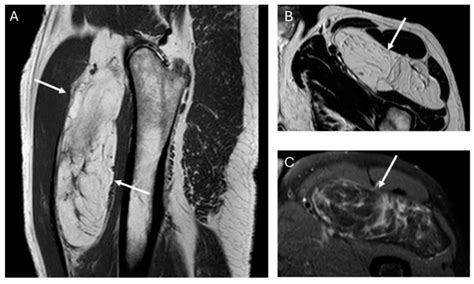

In contrast, a liposarcoma is a malignant (cancerous) tumor that arises from fat cells. Unlike lipomas, liposarcomas are rare. They belong to a category of cancers known as soft tissue sarcomas. While lipomas occur near the surface, liposarcomas often develop deep within the soft tissues of the body, such as deep in the thigh, the retroperitoneum (the area behind the abdominal cavity), or the limbs.

• MRI (Magnetic Resonance Imaging): This is the gold standard for evaluating soft tissue masses. It provides detailed images that help radiologists distinguish between simple fat tissue and more complex, suspicious-looking tumors.

• liposarcoma vs lipoma mri